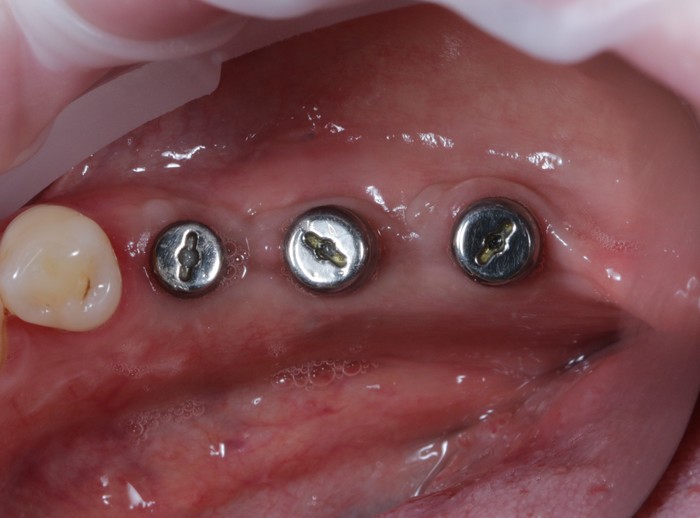

Вот пример того, когда пациент пренебрёг данным правилом:

Мужчине были установлены и спротезированы (временными коронками) имплантаты в другой клинике. После этого он пропал на несколько лет, не закончив полностью свое лечение. Явился лишь тогда, когда почувствовал «дискомфорт».

Кроме несостоятельности старых коронок и пломб, патологической стираемости зубов и т.д. - все эти годы сильно страдала гигиена.